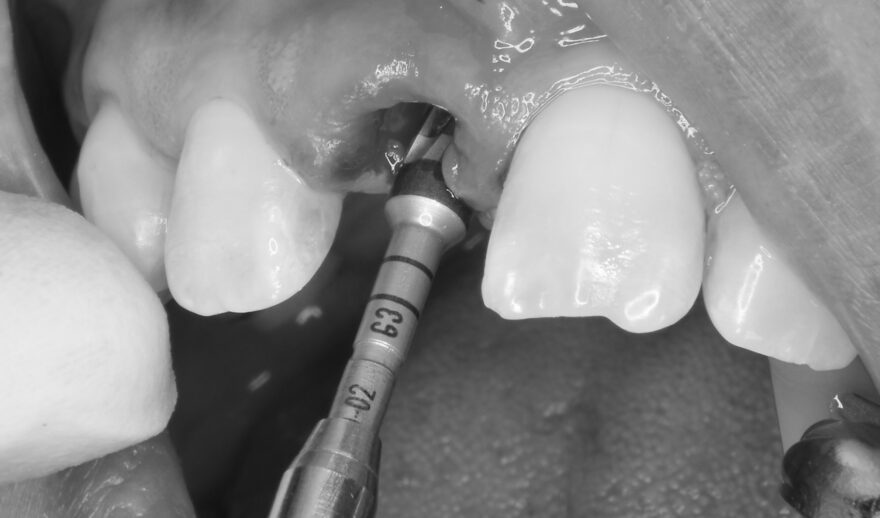

オペ中の口腔内写真とCT写真